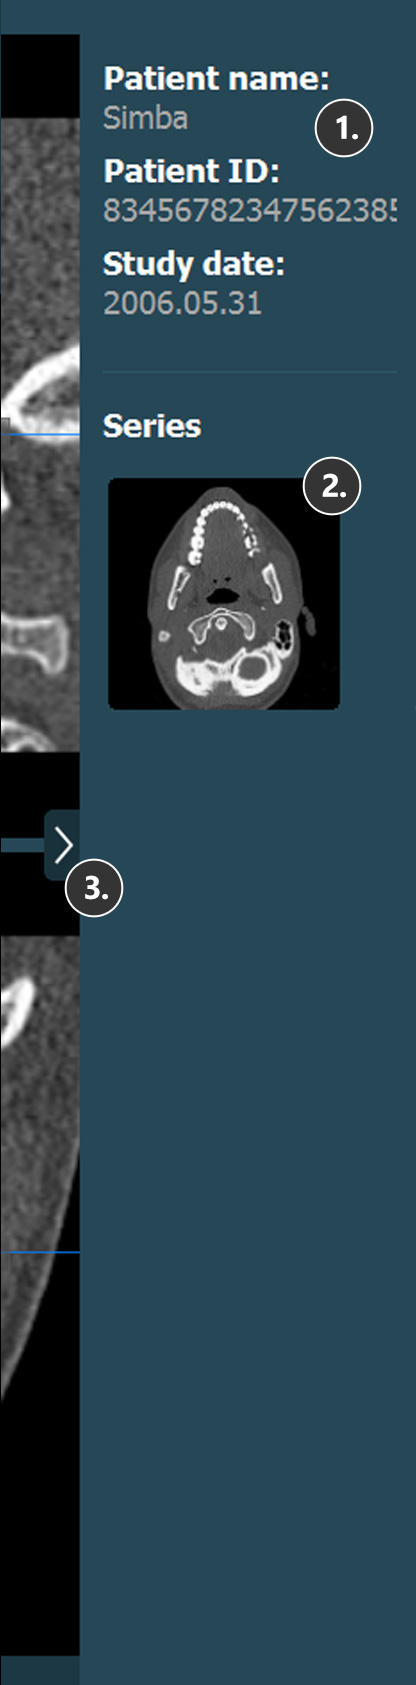

Patienteninformationen

Studieninformationen